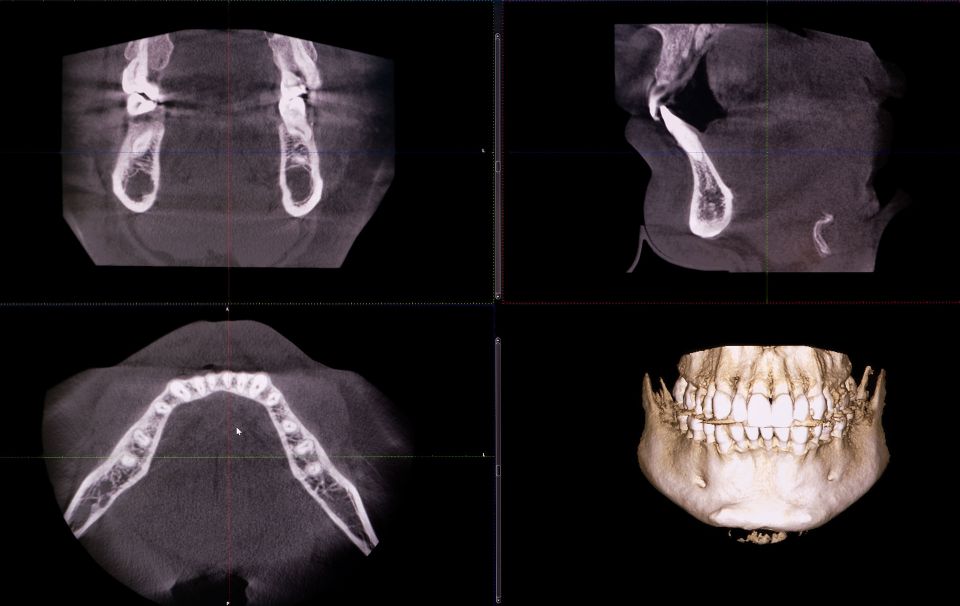

Eine Besonderheit bei Sylt Dental: Wir planen Ihre Implantate virtuell an einer 3-dimensionalen Röntgenaufnahme. Dafür setzen wir einen sogenannten digitalen Volumentomographen (DVT) ein. Dieses Diagnose- und Planungsverfahren bietet erhebliche Vorteile und vor allem Sicherheit für Sie als Patient!

Anhand des dreidimensionalen digitalen Röntgenbilds wird die Kieferhöhlenanatomie exakt dargestellt und auch Gefäße lassen sich genau lokalisieren. Wir erkennen z.B. die Breite und Knochendichte Ihres Kiefers, können die genaue Lage benachbarter Zahnwurzeln oder die Lage der Nerven bestimmen. Mit diesen präzisen Informationen planen wir mit einer speziellen Software die exakte Platzierung des Implantats. Am Bildschirm simulieren wir für Sie vor der Behandlung, wie Ihre neuen Zähne aussehen werden.